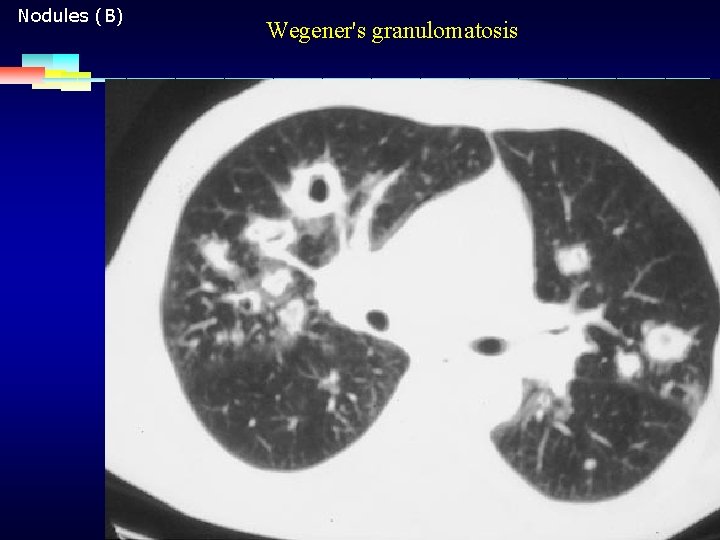

Nodules (B) Wegener's granulomatosis 2007